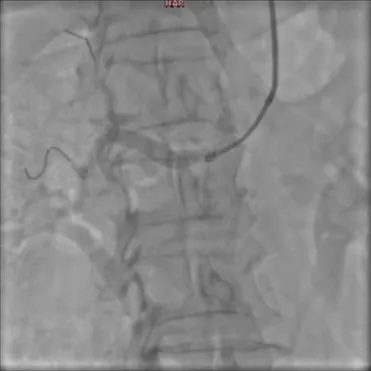

1. Начало операции